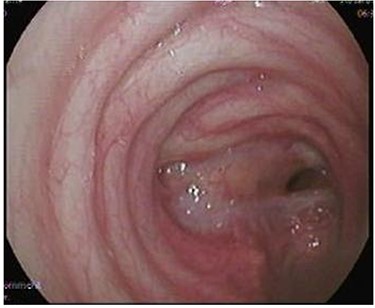

After discharge, the patient presented to the Emergency Room with shortness of breath and tachypnea. Chest X-rays and CT scan were unremarkable; however, he was admitted with type 2 respiratory failure and placed on noninvasive ventilation. Due to persistent tachypnea, the patient’s initial CT scans were reassessed with reconstruction and showed a complete transection of the trachea that was overlooked initially (Fig. 2). Flexible bronchoscopy revealed a significant post-traumatic tracheal stenosis (Fig. 3). It was tight stenosis (2 cm length on the CT reconstruction) and just above the carina. The patient was taken to the OT, with the ECMO team on standby. During rigid bronchoscopy, the patient became more hypoxic, and VV-ECMO was instituted. The stenosis was dilated with a small (#6) endotracheal tube (ETT) placed across the stenosis. He subsequently returned to the OT for further dilation and placement of a # 7.5 ETT. After 9 days, bronchoscopy revealed no gross residual stenosis and therefore the patient was successfully extubated. The patient was removed from ECMO support on the following day. After several days, the patient developed tachypnea, tachycardia and a respiratory acidosis. He was reintubated and shifted to the OT again (with ECMO standby) for redilation of restenosis with a #8 ETT in place. A covered tracheal stent was placed intraoperatively via rigid bronchoscopy (Fig. 4 A–C). Later on, the patient was extubated and eventually discharged home in stable condition.